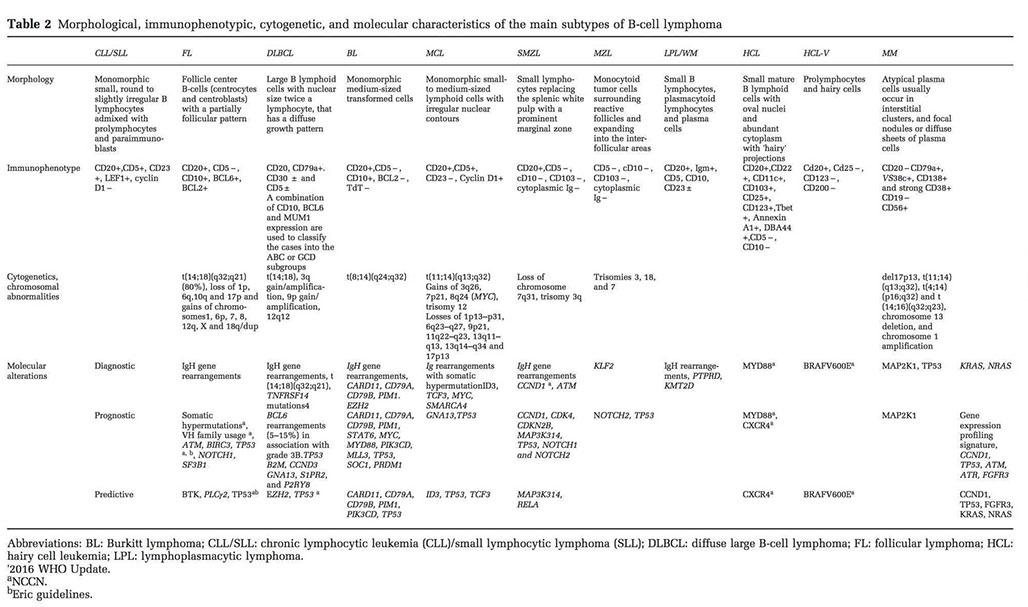

Chronic Lymphocytic Leukemia/Small Lymphocytic Lymphoma (CLL/SLL)

Monomorphic, mono-/oligoclonoal small round B-lymphocytes in lymph tissue (spleen, LNs), BM, PB which are CD5/23 (+)

- MCC leukemia in adults in Western countries (very low in Eastern countries [= genetically inherited?]); 2:1 M:F ratio; avg age 65 years

IHC

(+) IgM/D2, CD5 (>3/4)/11c/19/20 (dim) / 22/23/43/79a, Bcl-2, PAX5

- neg: CD10/79b/81, FMC7 (dim to neg), cyclin D1 (Bcl1)

-- proliferation centers can be cyclin D1+ in up to 30% of CLL/SLL

- CD23+/FMC7- can differentiate CLL/SLL from MCL in most but not all cases

- atypical profiles have CD5/23 (-); CD11c/79a/FMC7

Should ALWAYS do Cyclin D1 on new cases of CLL to make sure it is not mantle cell lymphoma

- having some Cyclin D1 positivity in the proliferation centers can be seen in up to 30% of cases , especially in the subset of CLL/SLL with CONFLUENT proliferations centers (tend to behave more aggressively)

- some mantle cell lymphomas can have small round nuclei

MYC is often increased usually in proliferation centers (sometimes with inc Ki67)

New IHC markers in CLL:

LEF1 - a highly specific martker for CLL/SLL (+ in ~100%, but also + in some larger lymphomas (DLBCL and HG-FL) and is positive in T-cells

CD200

Useful diagnostic marker

Bright in CLL, dim/- in mantle cell lymphoma

CD49d

Useful prognostic marker (better than CD38)

>30% of clonal B-cells+ = CD49d+

CD49d+ 10 yr OS probability 62% vs 84% for CD49d- (Bulian et al. J Clin Oncol . 2014;32:897-904)

Flow: small FMC7 neg B-cells, CD20 dim, light chain dim

Genes: rearranged IG genes unmutated in 1/2, and mutated in 1/2 of cases; are clinically different

- tyrosine kinase ZAP-70 or CD38 expression assoc c unmutated CLL IGHV gene (has not gone through the GC), and thus an aggressive clinical course and poor px

80% have FISH abnormality (50% have del13q14.3, 20% trisomy 12)

- BM involvement has poor px

- trisomy 12 has intermed px

Genes: MC abnormality is normal (1/2), then trisomy 12 (1/3, atypical cells, adverse px), then del13q14 (~1/4, has good px)

- large number of mutations that occur with low freq

- FISH may have del 13q14 (>1/2), also tri 12, del(11q), del(14q), del(17p); 1/5 normal by FISH

-- del 13 and trisomy 12 have good px, del 11q and 17p have a poor px

Px: uses Rai/Binet staging system

- Pts c mutated CLL (IgHV [see below]) have better px than unmutated CLL

- (+) ZAP-70 and CD38 assoc c poor px; VH3-21 also poor px; 11q deletion is poor px

- CLL cells have uniform Ig heavy chain variable (IgHV) genes, which most likely came from single precursor cell prolif.

- px affected by high stage, B-sx, diffuse BM involvement, doubling time <1 yr in PB, high initial lymph count (>30k), unmutated Ig HC variable region (IgVH) [ CLL c unmutated IgVH resembles pregerminal center B-cells, is likely to progress, poor px, can be tx'd, have ZAP-70/CD38 expression]

- Proliferation centers that are large / confluent and have a high proliferation fraction are a significant and independent adverse prognostic indicator